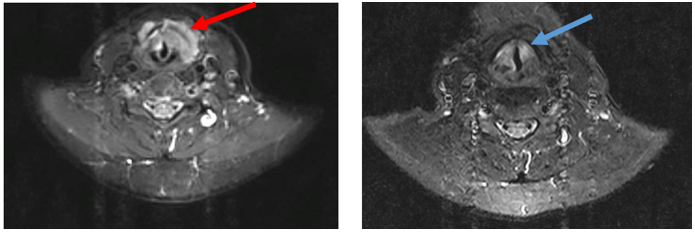

3.     Biến đổi trên chẩn đoán hình ảnh (trước và sau điều trị)

Hình ảnh MRI cổ: Hình ảnh tổn thương vùng hạ họng thanh quản giảm kích thước sau điều trị 3 tháng, từ 41 x 22mm (mũi tên đỏ) xuống còn kích thước 20 x 13mm (mũi tên xanh).

-         Sau 3 tháng, khối u hạ họng - thanh quản giảm kích thước còn 20 x 13mm, bệnh nhân cải thiện triệu chứng lâm sàng.